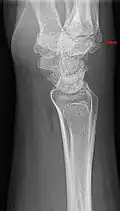

The joint between the index metacarpal and the capitate is a fibrous non-mobile joint. Some people have a gene that leads to this growth. It looks like arthritis (bone spurs on each side of the joint) on X-ray. It looks like a ganglion on the hand, but more towards the fingertips.

Carpometacarpal boss is uncommon and there is not much scientific data. Its etiology has yet to be fully defined, but can be congenital in the form of an accessory ossicle (os styloideum) or may be acquired from trauma, repetitive use, or degenerative osteophytosis.[3] The condition usually begins to show in the 3rd or 4th decade.